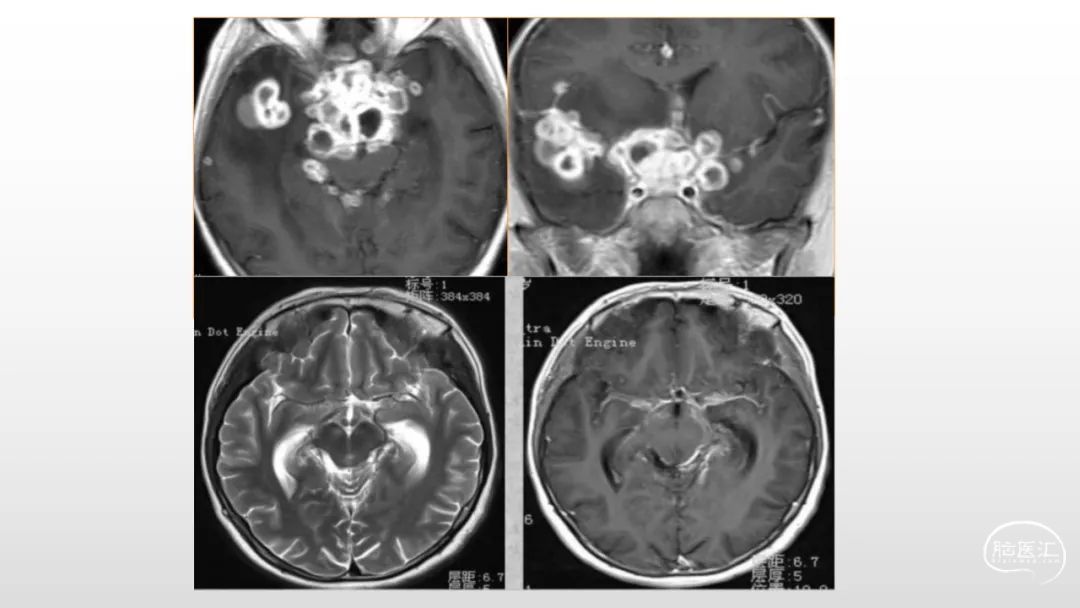

颅脑影像诊断基础知识讲座:感染和免疫性疾病1